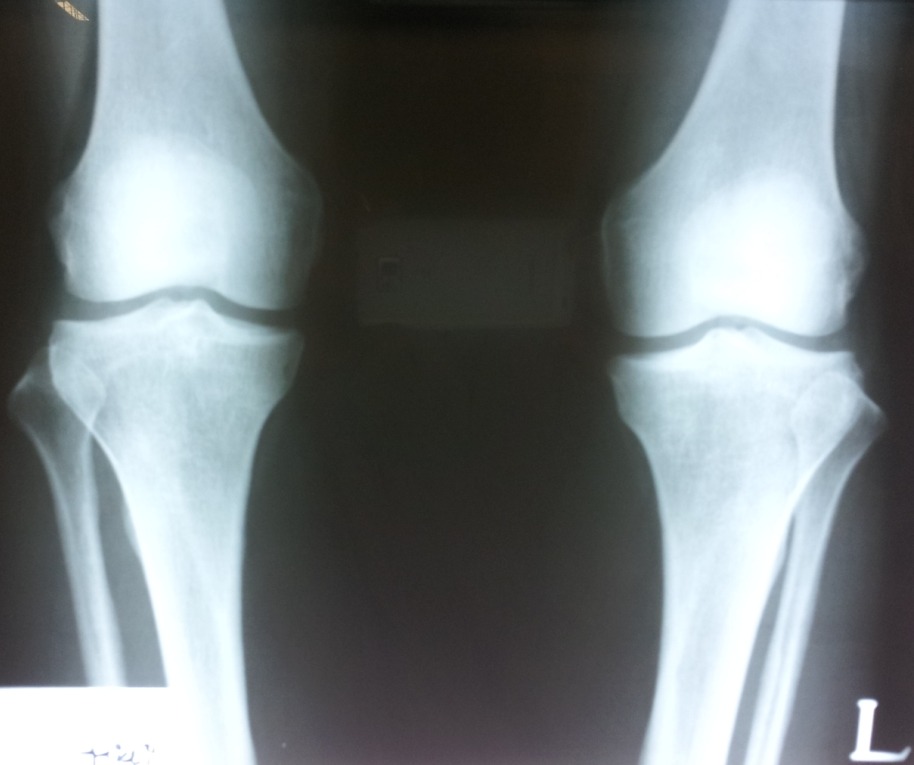

lt knee caption(patella) lateral subluxation - static 평가